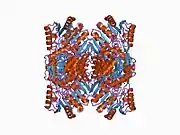

The enzyme encoded by the human ALDH2 gene is a tetrameric enzyme that contains three domains; two dinucleotide-binding domains and a three-stranded beta-sheet domain. The active site of ALDH2 is divided into two halves by the nicotinamide ring of NAD+. Adjacent to the A-side (Pro-R) of the nicotinamide ring is a cluster of three cysteines (Cys301, Cys302 and Cys303) and adjacent to the B-side (Pro-S) are Thr244, Glu268, Glu476 and an ordered water molecule bound to Thr244 and Glu476.[11] Although there is a recognizable Rossmann fold, the coenzyme-binding region of ALDH2 binds NAD+ in a manner not seen in other NAD+-binding enzymes. The positions of the residues near the nicotinamide ring of NAD+ suggest a chemical mechanism whereby Glu268 functions as a general base through a bound water molecule. The sidechain amide nitrogen of Asn169 and the peptide nitrogen of Cys302 are in position to stabilize the oxyanion present in the tetrahedral transition state prior to hydride transfer. The functional importance of residue Glu487 now appears to be due to indirect interactions of this residue with the substrate-binding site via Arg264 and Arg475.[12]

The inactivating ALDH2*2 mutation is "the most common single point mutation in humans".[15] This mutation is found in very few White people, but about 50% of East Asians are heterozygous for this mutation. The ALDH2*2 allele encodes lysine instead of glutamic acid at amino acid 487,[16] distorting the NAD+ binding site.[17][18] ALDH2 assembles and functions as a tetramer and requires all four of its components to be active in order to metabolize acetaldehyde. People heterozygous for ALDH2*2 have only 10% to 45% enzyme activity, while those hymozygous for ALDH2*2 have as little as 1% to 5% remaining activity.[19]